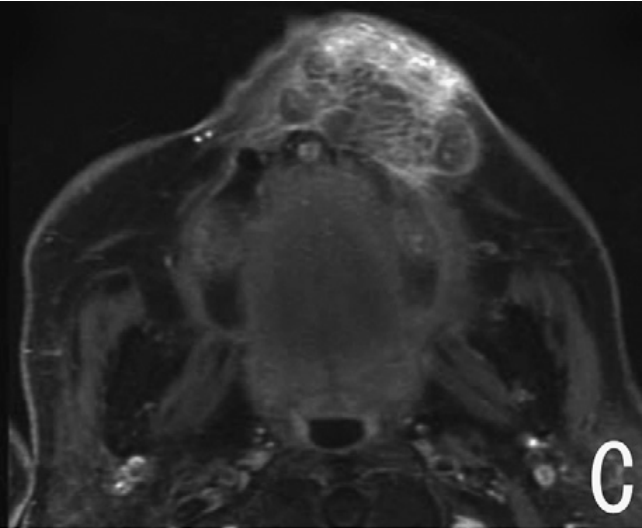

当常规治疗手段宣告效果不佳,肿瘤仍在体内肆虐时,患者心中的绝望难以言表。放疗、化疗带来的副作用还未褪去,身体的疼痛却日夜加剧,吃饭、睡眠这些最基本的生活需求都成了奢望。近日,东莞的一家医院成功应用国产首台直线型射频四极场硼中子俘获治疗(RFQ-BNCT)系统完成了一例复发鼻咽癌患者的全流程治疗。这个消息就像是一颗重磅炸...